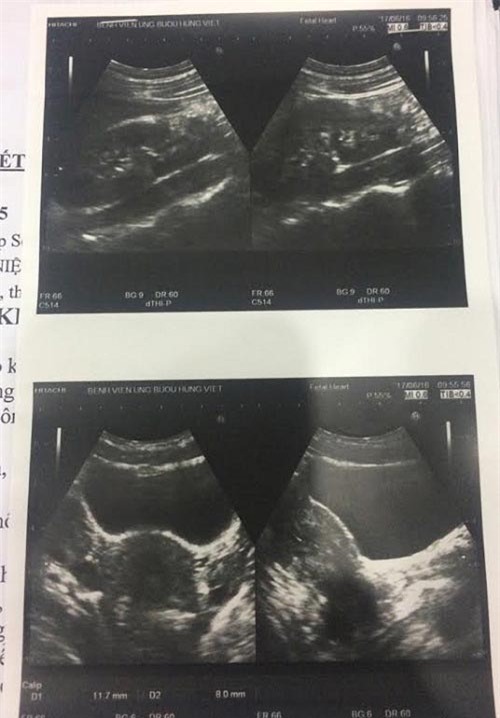

Hình ảnh siêu âm ổ bụng của bệnh nhân Hiền sau khi được phẫu thuật.

Bệnh nhân Nguyễn Thị Hiền đã được các bác sĩ phẫu thuật cắt bỏ quả thận và niệu quản thừa, bảo toàn được hai thận chính. Sau mổ, bệnh nhân ổn định, dự kiến sẽ được xuất hiện trong vài ngày tới.

Người có ba quả thận rất hiếm gặp nếu như các thận hoạt động bình thường thì sẽ không ảnh hưởng đến sức khỏe bệnh nhân. Tuy nhiên với trường hợp của bệnh nhân Hiền, thận phụ phải đã teo nhỏ, chức năng thận bị hạn chế rất nhiều và có dấu hiệu ứ nước nên cần loại bỏ ngay.